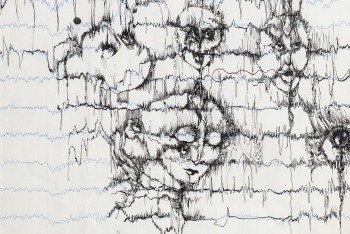

Im Bilderlager der UPK Basel sind auch Arbeiten der Schauspielerin und Zeichnerin Béatrice (Bea) Schweizer (1936–2013) bewahrt. Ihr künstlerisches Werk umfasst rund 600 Bilder, klein- wie grossformatige, und nimmt in der Sammlung der UPK den grössten Umfang ein. Auch formal und inhaltlich handelt es sich um ein eigenwilliges Werk. Es ist vielseitig und zeigt ihr Können. Es liegt nahe, dass Béatrice Schweizer eine künstlerische Ausbildung absolviert haben könnte. Eine Werkgruppe steht im Zentrum der Ausstellung: Zarte Zeichnungen mit schwarzer Tinte auf Registerpapier für EEG-Diagramme. Béatrice Schweizer nutzt den Verlauf der nervösen Kurven der gemessenen elektrischen Aktivität des Gehirns mit ihren unterschiedlichen zackigen Ausschlägen. Sie folgt den Kurven, fährt in rasanten Bewegungen darüber hinaus, verdichtet ihre Striche zu eingeschwärzten Partien, aus denen sich Figuren entwickeln. Beherrscht wird ihr Werk von Motiven des Dämonischen. In den Zeichnungen erscheinen sie wie in das Diagramm eingeschrieben, als würden sie aus den eigenen Hirnströmen herausfliessen und auf dem Papier Gestalt annehmen. Es lässt sich nur mutmassen, mit welchen inneren Dämonen Béatrice Schweizer kämpfte.